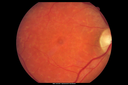

65 year old woman with gradually declining central vision. VA 20/200 in both eyes in the later photos (left eye was better in earlier photos). FAF shows pisciform tri-radiate lesions that are hyper FAF typical of stargardt's fundus flavimaculatus

Stargardt's Macular Dystrophy ABCA4 positivevaatamisi: 530Images show some progression over 3 years of macular dystrophy.00000

Stargardt's Macular Dystrophy ABCA4 positivevaatamisi: 483Images show some progression over 3 years of macular dystrophy.00000

Stargardt's Macular Dystrophy ABCA4 positivevaatamisi: 572Images show some progression over 3 years of macular dystrophy.00000